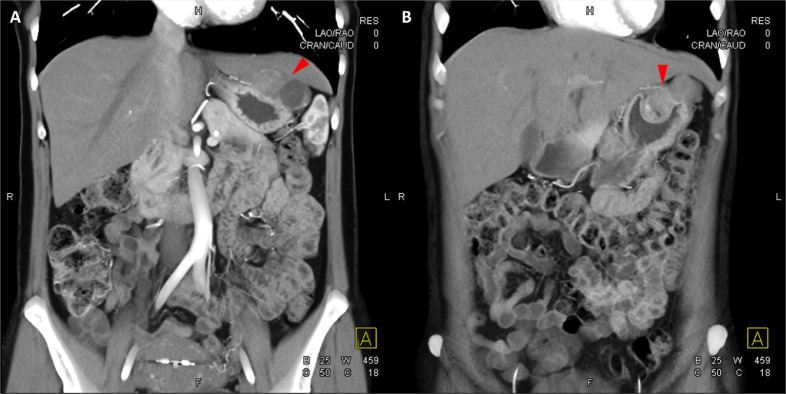

胸部、腹部和骨盆的對(duì)比增強(qiáng)動(dòng)脈和靜脈期 CT 顯示多個(gè)圓形、主要是血管豐富的異質(zhì)腫塊,具有囊性和實(shí)性成分,起源于胃底和胃體(圖 2-4)。 病變部分呈外生結(jié)構(gòu),被認(rèn)為位于粘膜下層。 在頸部多發(fā)同步性副神經(jīng)節(jié)瘤的情況下,賊初的鑒別診斷包括多發(fā)性副神經(jīng)節(jié)瘤、多發(fā)性 GIST 以及轉(zhuǎn)移性疾病。

Fig. 2

圖 2:多發(fā)胃腸道間質(zhì)瘤的軸位 CT 圖像。 (A 和 B)軸位動(dòng)脈相增強(qiáng) CT 圖像和(C 和 D)軸位靜脈相增強(qiáng) CT 圖像顯示多個(gè)圓形、不均勻、增強(qiáng)的腫塊,具有實(shí)性和囊性成分。 腫塊位于粘膜下,結(jié)構(gòu)呈外生。

Fig. 3

圖 3:多個(gè)胃腸道間質(zhì)瘤的冠狀和矢狀圖像。 (A 和 B)冠狀動(dòng)脈相對(duì)比增強(qiáng) CT 圖像顯示胃賁門(mén)產(chǎn)生的外生性腫塊。 (C 和 D)矢狀動(dòng)脈相位對(duì)比增強(qiáng)圖像顯示腫塊的異質(zhì)性和外生結(jié)構(gòu)。

Fig. 4

圖 4: 胃腸道間質(zhì)瘤的三維表示。 (A 和 B)胃腸道間質(zhì)瘤在動(dòng)脈期和冠狀面的 3D 可視化提供了進(jìn)一步的解剖細(xì)節(jié)和空間信息。